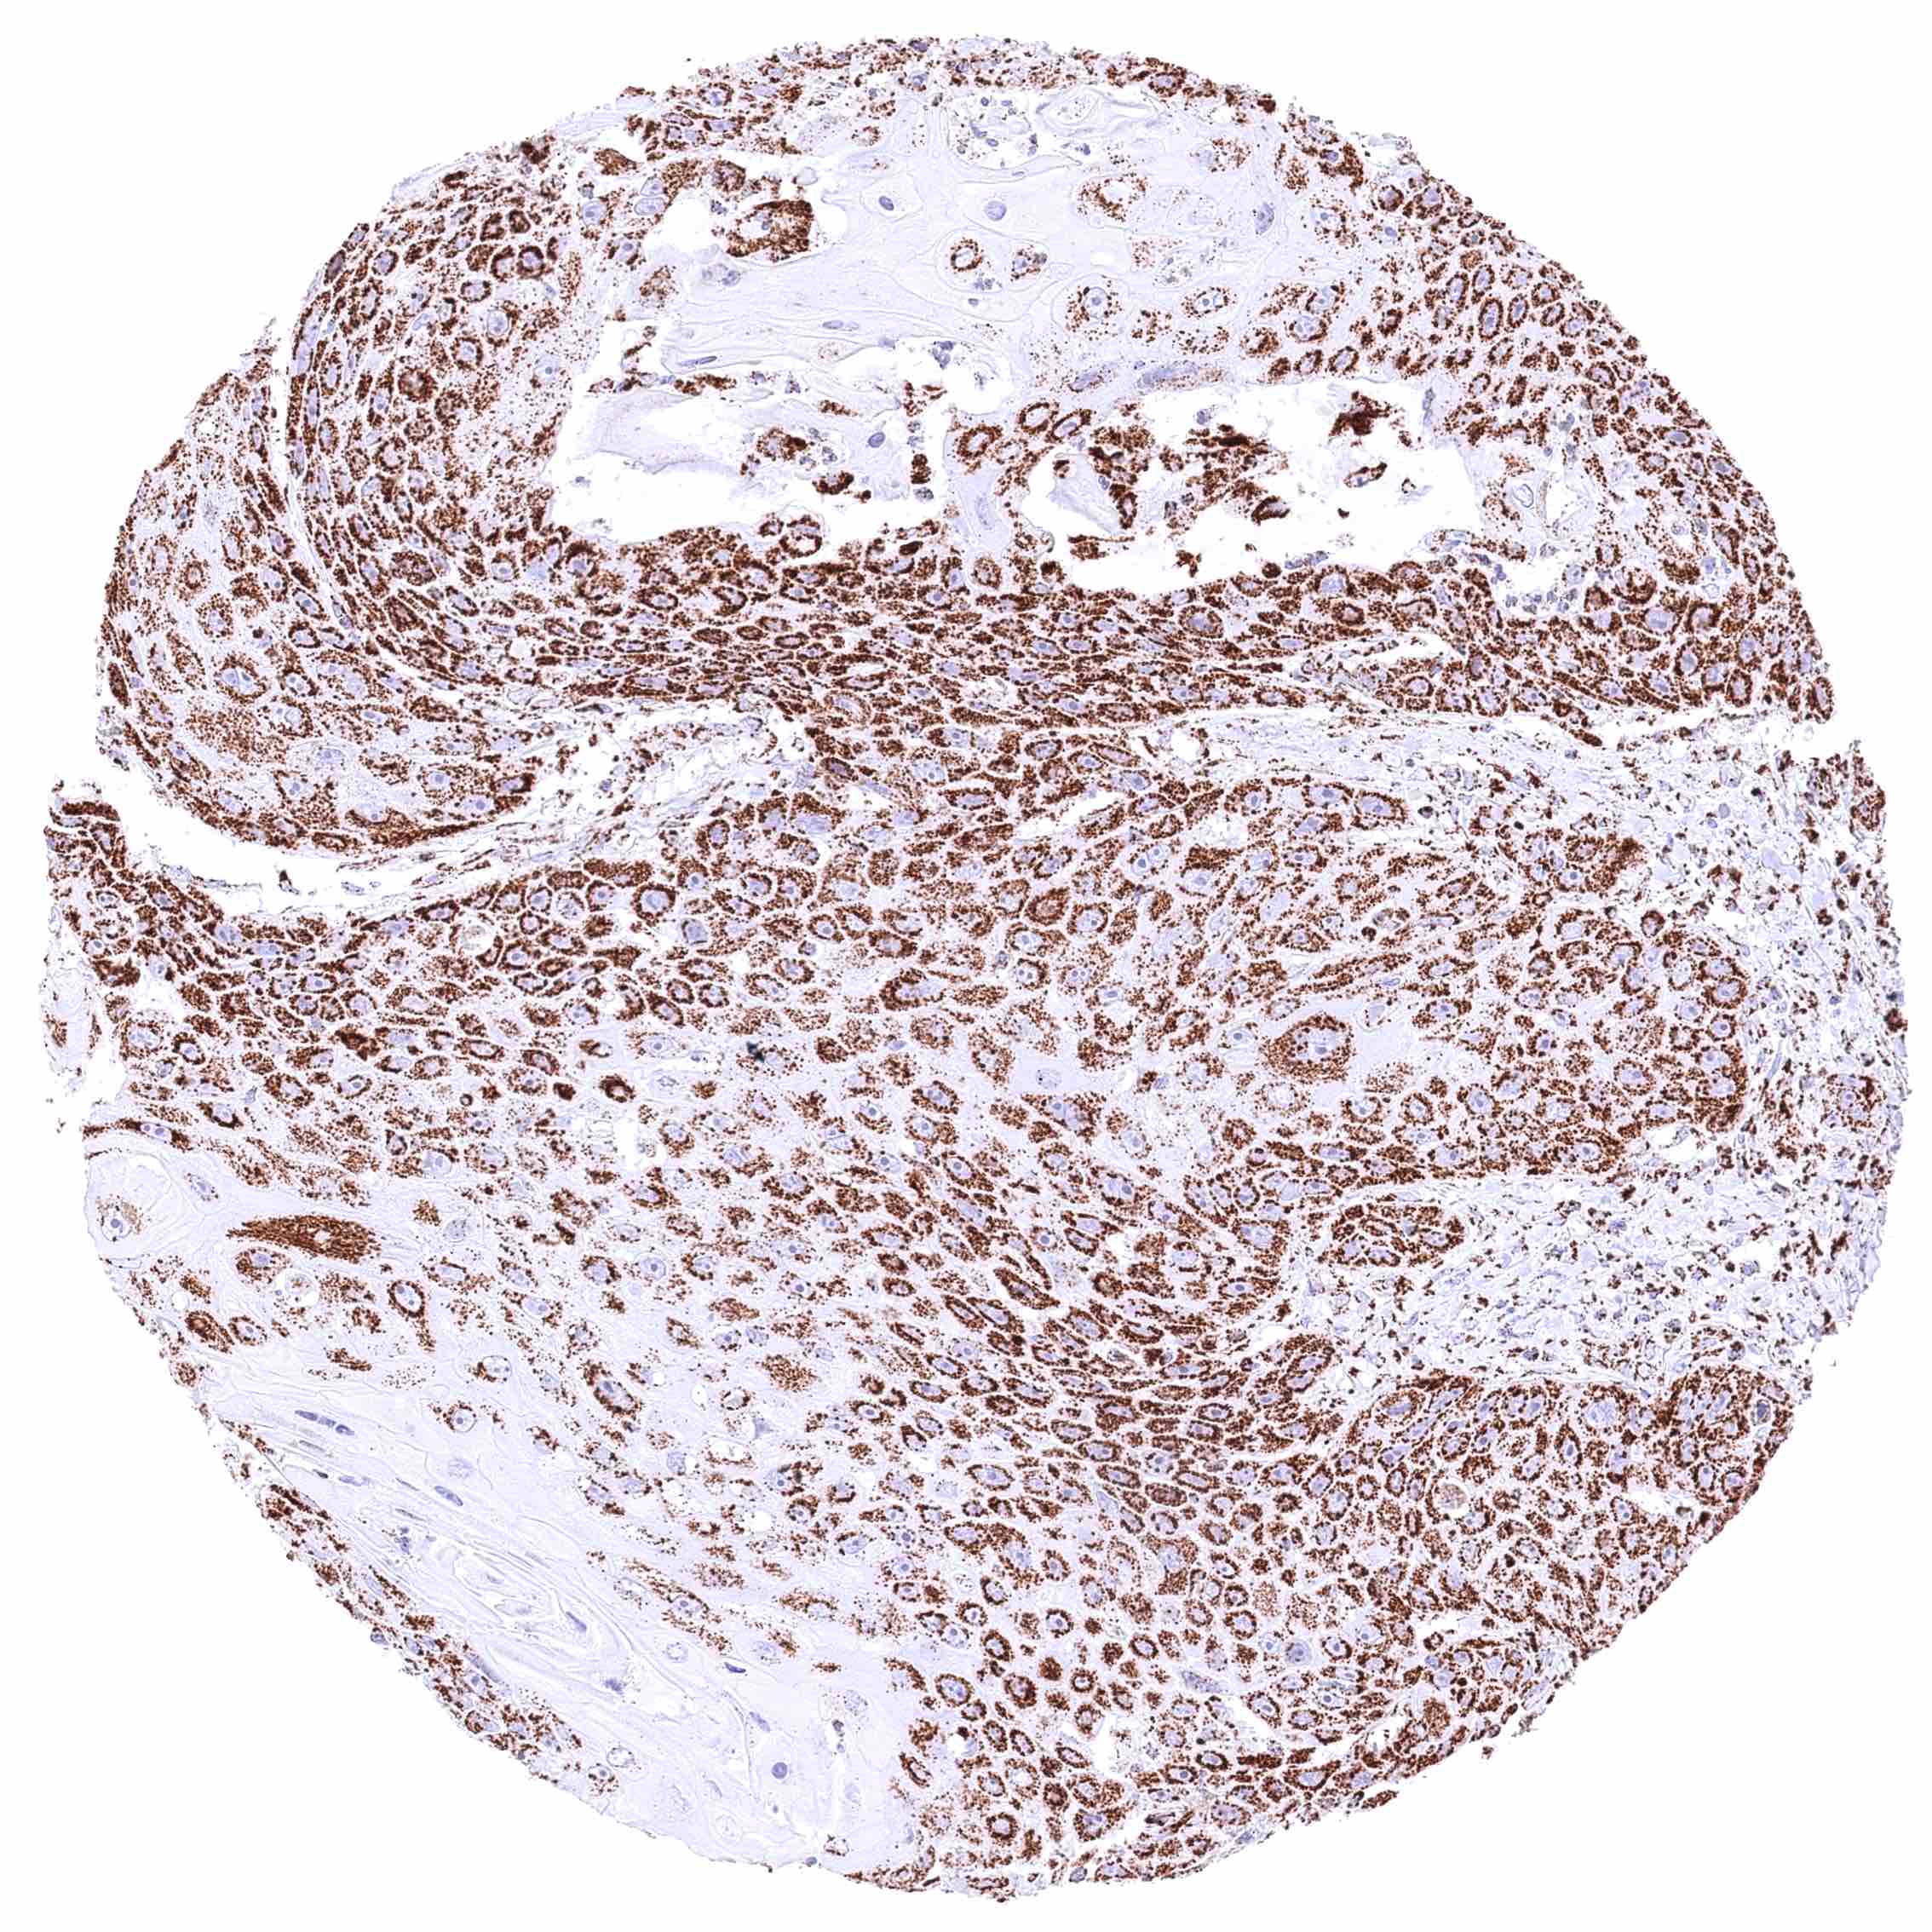

Prostate – Adenocarcinoma (Gleason 5+5=10) with intense cytoplasmic ATP5J positivity of all tumor cells.